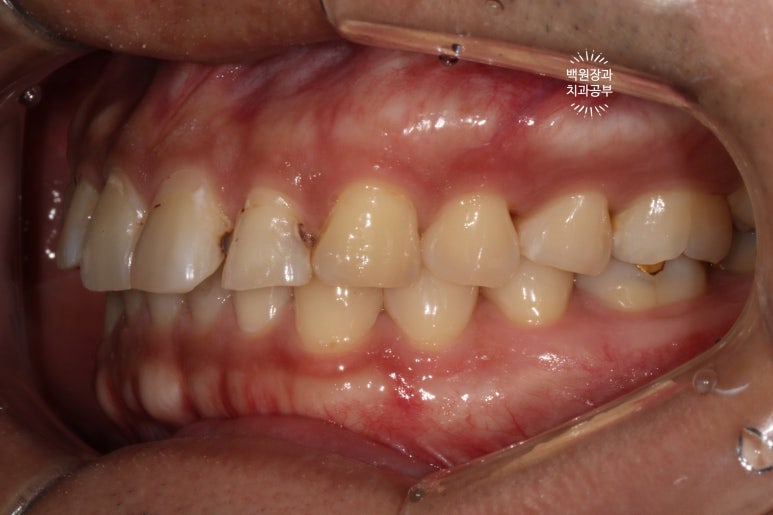

고개를 돌려 좌측을 보시면, 우측에서 보이던 것과 달리 치아 표면이 깨져서 구멍이 나신 것을 보실 수 있죠?

교합면에서 보면, 충치가 뒤에서 봤을 때도 까맣게 보이는구나~ 라고 아실 수 있을겁니다.